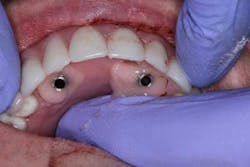

Surgery commenced. Implants on the lower arch were placed first (figures 7 and 8) and then we switched to the maxillary. The teeth were removed (figures 9 and 10) and the ridge was evened out (figures 11-13). The implants were aligned with the denture (figure 14) and then placed accordingly (figures 15-17). Healing caps were put on, and we were ready to start the restorative phase (figures 18-19).

The maxillary arch was indexed first as there was support from the palate to reference position (anterior/posterior) (figure 20). Then the lower was put into position to gain proper vertical dimension and occlusion. It, too, was then indexed; both upper and lower were given to the lab technician to start the conversion process. Next, impression copings were placed (one arch at a time) and secured with paperclips; a full-arch PVS impression was taken and likewise sent to the lab (figures 21-23). Finally, after the conversion process was completed, the bridges were secured in place on the multiunit abutments, torqued to 15nCm, and covered. Bite was adjusted and follow-up care was arranged (figures 24-26).